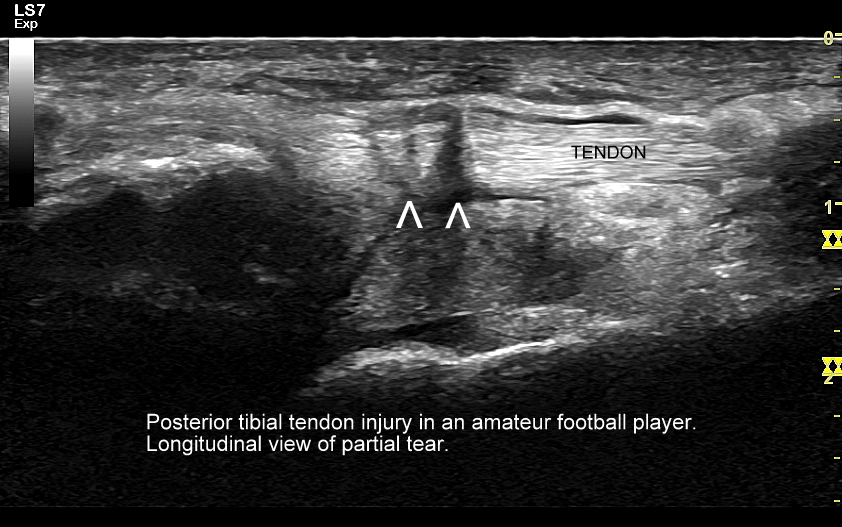

USG łydki i podudzia najczęściej służy ocenie różnorodnych urazów, których sztandarowymi przykładami są łydka tenisisty, czy naderwanie / zerwanie ścięgna Achillesa. Dr Szczepański spotyka się w swojej praktyce również z szeregiem rzadkiego typu urazów i patologii takich jak przewlekły zespół ciasnoty przedziałów powięziowych, naderwania ścięgien zginaczy, przeciążenie troczków ścięgien, shin-splint, złamania przeciążeniowe kości, malformacje naczyniowe, zmiany nowotworowe, ciała obce, czy infekcje tkanki podskórnej, powięzi, a nawet mięśni.

USG jest wysoce przydatną oraz metodą diagnostyczną pierwszego wyboru przy ocenie szeregu zmian chorobowych toczących się w obrębie stopy, w tym urazowych, przeciążeniowych, zapalnych, infekcyjnych, metabolicznych, czy nowotworowych. Przykładem najczęściej występującego urazu stopy, potocznie nazywanego skręceniem kostki występującego w wyniku inwersji stopy, jest naderwanie więzadła skokowo-strzałkowego przedniego (ATFL). Zmiany urazowo-przeciążeniowe dotyczyć mogą jednakże praktycznie każdego elementu. Dr Szczepański diagnozował w USG stopy m. in. takie patologie jak złamanie kości strzałkowej, złamanie trzeszczek, naderwania i zerwania ścięgien, czy przeciążenia troczków. W USG można ocenić również unaczynienie stopy, powikłania stopy cukrzycowej, zapalenie stawów w przebiegu dny moczanowej i reumatoidalnego zapalenia stawów, a także nowotwory stopy, w tym włókniaka rozścięgna podeszwowego (choroba Ledderhose’a).